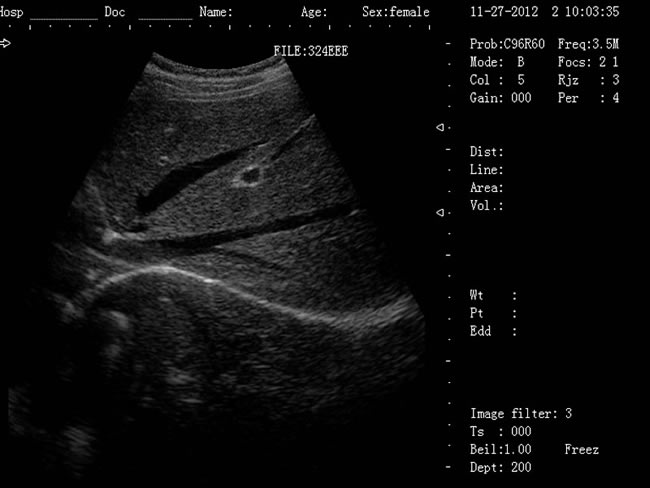

| 老式的b超機(jī)黑白要多少錢?已被新型B超機(jī)所取代! |

老式的b超機(jī)黑白要多少錢?老式的B超機(jī)是CRT顯示器,CRT顯示器學(xué)名為“陰極射線顯像管”,是一種使用陰極射線管的顯示器。現(xiàn)在科技進(jìn)步,已經(jīng)慢慢被新型顯示器所取代。老式的黑白b超機(jī)CRT顯示器主要有五部分組成:電子槍,偏轉(zhuǎn)線圈,蔭罩,高壓石墨電極和熒光粉涂層及玻璃外殼。感謝大家對我司CRT顯示器相關(guān)產(chǎn)品長久以來的支持與厚愛,該系列機(jī)型因順應(yīng)市場的需求,已經(jīng)無法滿足客戶的生產(chǎn)需求。該系列機(jī)型正式停產(chǎn),后期不再供應(yīng)該型號的儀器。給廣大的新老客戶造成的不便敬請諒解。應(yīng)廣大用戶的需要,CRT相關(guān)產(chǎn)品的售后服務(wù)依然支持,同時(shí)保留儀器后期的維修部件。

徐州大為DW-500筆記本b超機(jī) 1、DW-500產(chǎn)品特點(diǎn): (1)DW-500是一款高陣元、高清晰度、多功能的筆記本式超聲診斷儀。 (2)它的小巧輕便,圖像清晰,操作方便、續(xù)航能力強(qiáng),在城市、鄉(xiāng)鎮(zhèn)、戶外等,各種環(huán)境下會(huì)診的超強(qiáng)優(yōu)越性。 (3)多種充電方式更保證了在不同環(huán)境下檢查會(huì)診。 2、DW-500新增3大看點(diǎn): (1)5-7小時(shí)超長待機(jī)時(shí)間 (2)12.1英寸LED液晶顯示器 (3)全數(shù)字96陣元 3、一流的數(shù)字成像技術(shù),圖像更清晰 (1)DBF全數(shù)字波束形成 (2)DRF實(shí)時(shí)逐點(diǎn)動(dòng)態(tài)接受聚焦 (3)DRA實(shí)時(shí)動(dòng)態(tài)聲速變跡 (4)THI組織諧波成像 (5)RDA實(shí)時(shí)動(dòng)態(tài)孔徑成像 (6)DFS數(shù)控動(dòng)態(tài)頻率掃描 (7)RDF實(shí)時(shí)動(dòng)態(tài)濾波 4、靈活方便的操作系統(tǒng) (1)12.1英寸LED液晶顯示器 (2)背光硅膠鍵盤,更舒適耐磨,暗室中使用不再煩惱 (3)智能化菜單,人機(jī)對話輕松快捷 (4)顯示穿刺引導(dǎo)線,角度和位置可調(diào) (5)多倍率顯示,病變診斷更準(zhǔn)確 (6)外接USB存儲,圖像上傳更方便 (7)大容量的電影回放,圖像自動(dòng)循環(huán)演示 (8)豐富的測量功能:距離,周長,面積,體積,產(chǎn)科測量表,心臟軟件包等 (9)顯示模式:B、B+B、4B、B+M、M (10)電影回放:≥256幀,可連續(xù)回放或逐幅查看 (11)具有穿刺引導(dǎo)功能,穿刺線位置可調(diào)節(jié) (12)具有碎石定位,動(dòng)態(tài)靶區(qū)跟蹤功能 (13)主機(jī)尺寸:330x289x70mm(長x寬x高);